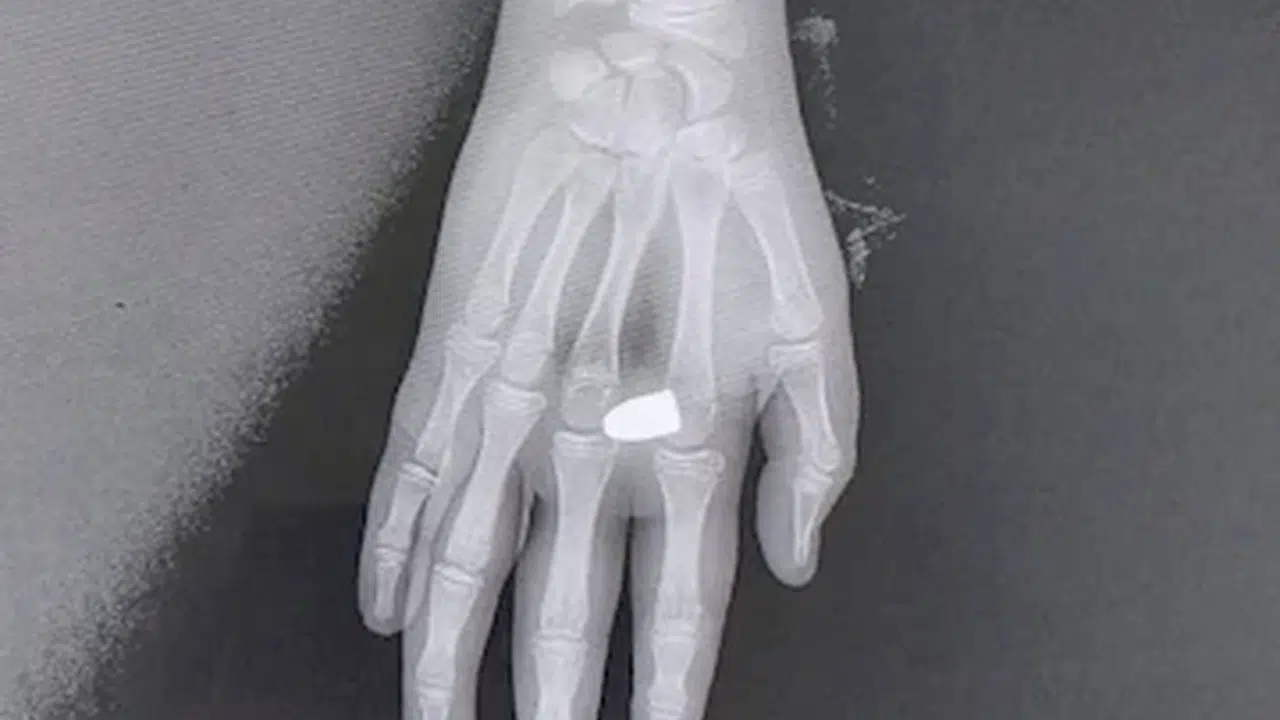

Tezcan SOLMAZ/KAYNAŞLI(Düzce),(DHA)-DÜZCE'nin Kaynaşlı ilçesinde eline yorgun mermi isabet eden Alperen K. (13) yaralandı.

Olay, dün sabah saatlerinde Kaynaşlı ilçesine bağlı Dipsizgöl köyünde meydana geldi. 'Bayram geleneği' adı altında bazı köy sakinleri, balkonlarından ve camlarından tabancalarla ateş açtı. Tabancaların birinden çıkan yorgun mermi, dışarıda olan Alperen K. isimli çocuğun sağ eline düştü. Alperen K., evine koşarak durumu ailesine haber verdi. Ailesi, kendi imkanlarıyla çocuğu Düzce Atatürk Devlet Hastanesi'ne götürdü. Burada, mermi çekirdeği doktorların operasyonuyla çıkarıldı. Olayla ilgili soruşturma başlatıldı. (DHA)

FOTOĞRAFLI